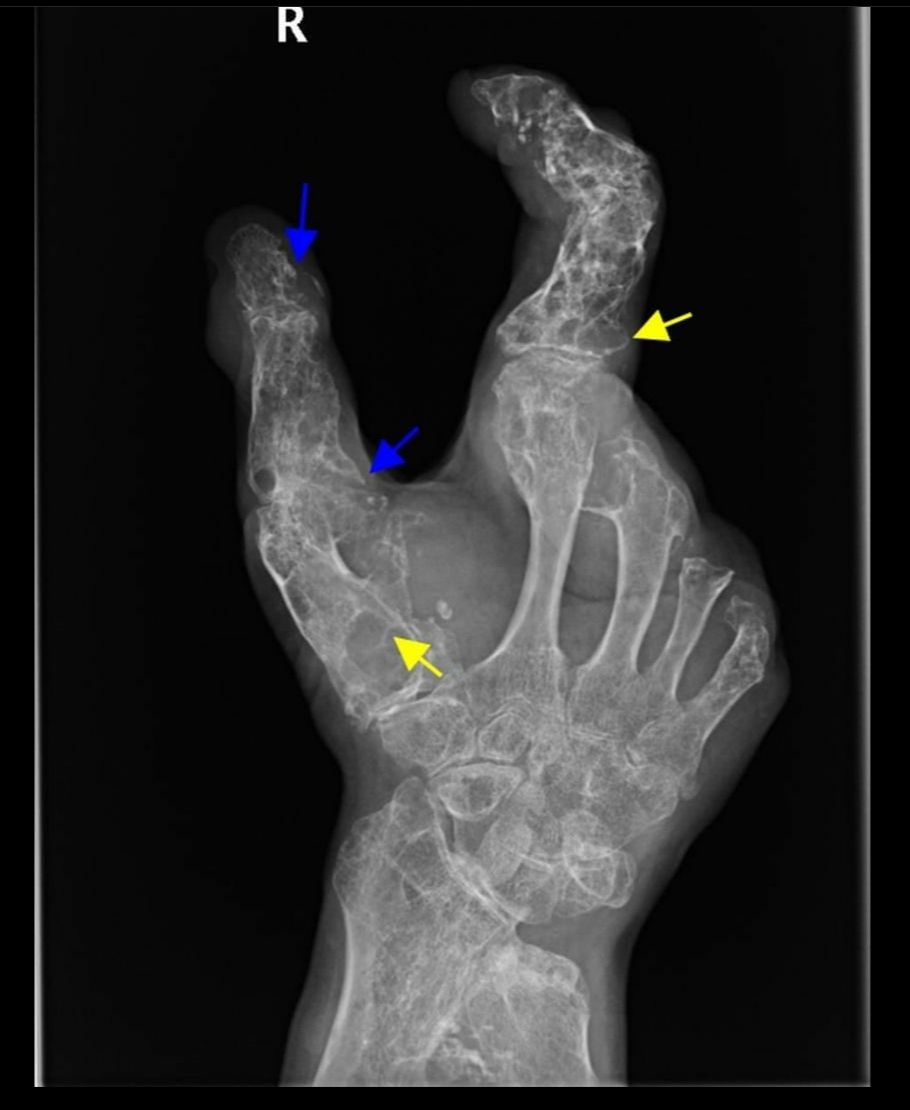

There are multiple lucent lesions, some with the classic rings and arcs calcification suggestive of chondroid lesions. There are areas of cortical destruction suggestive of extra-osseous extension of the lesions, which can be seen in the setting of malignant degeneration into chondrosarcoma.

The specimen contains multiple separate nodules of conventional type chondrosarcoma. These span up to 13 cm in greatest dimension and involve the distal radius, metacarpals of the thumb/index/long fingers, and phalanges of the thumb/index finger.

Physical exam: The distribution of disease is more prominent on the right side of the body. Status post amputations of the right length, ring, and little fingers. His thumb, palm, and wrist have multiple firm masses that cause skin tension and are tender to palpation.